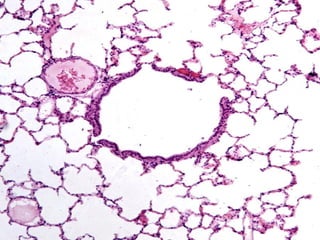

T A B I Q U E Epitelio simple planoalveolar y su lámina basal Tejido conectivo laxo: fibras reticulares y elásticas finas y abundante red capilar Epitelio simple plano alveolar y su lámina basal I N T E R A L V E O L A R

Neumocito tipo I(célula plana) Neumocito tipo II (célula alveolar) Células endoteliales Macrófagos alveolares Células sanguíneas (dentro de los capilares) Fibroblastos C É L U L A S D E L T A B I Q U E I N T E R A L V E O L A R

BARRERA SANGRE-AIRE Endotelio continuo delos capilares Membrana basal del capilar Zona difusa Membrana basal del neumocito tipo I Citoplasma de la célula epitelial alveolar Película del surfactante pulmonar Con frecuencia falta la zona difusa y se fusionan las membranas basales quedando reducida la barrera a tres elementos: Citoplasma adelgazado del endotelio capilar Membrana basal fusionada Citoplasma adelgazado de la célula epitelial